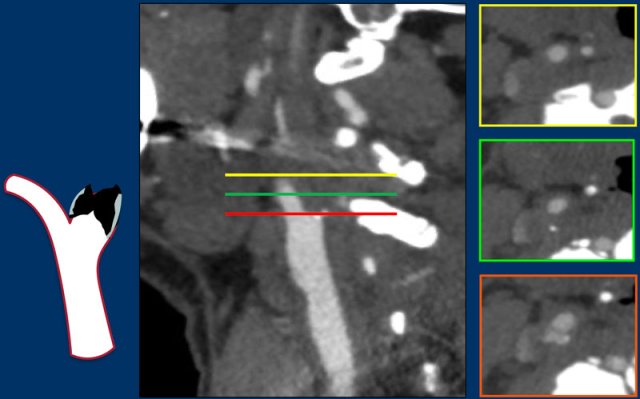

ICA stenosis measurement

The illustration shows the formula for measuring the degree of stenosis according to the NASCET (North American Symptomatic Carotid Endarterectomy Trial).

The diameter of the stenosis (a) should be measured perpendicular to the longitudinal axis of the vessel (green line) and not in a pure axial plane (red line), because then you may underestimate the degree of stenosis.

It is compared to the diameter of the normal vessel at about 6 cm distal to the stenosis (b).

In the formula the degree of stenosis is calculated.